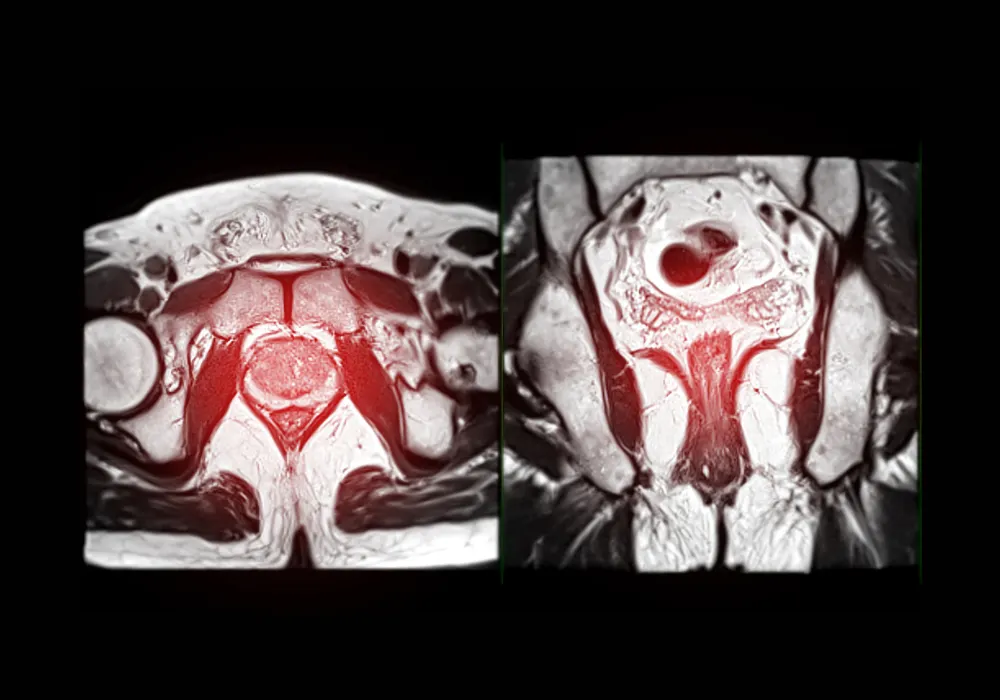

Magnetic resonance imaging has become central to prostate cancer diagnosis and risk stratification, yet variability in image quality can undermine clinical pathways. A multi-institutional analysis assessed how prostate imaging quality, graded with the updated Prostate Imaging Quality Score version 2 (PI-QUAL v2), affects the diagnostic performance of biparametric MRI (bpMRI) in detecting clinically significant prostate cancer. The investigation also examined which technical parameters most strongly influence image quality on T2-weighted and diffusion-weighted sequences. The findings highlight that suboptimal acquisition compromises sensitivity and that specific technical choices—particularly in-plane resolution on T2-weighted imaging and the number of b values for diffusion—are pivotal to achieving reliable results. These insights support efforts to standardise protocols and reinforce quality control before decisions are made on biopsy or surveillance.

The analysis included 112 men referred for second-opinion reads after bpMRI performed at 69 external facilities between January 2020 and November 2021. Images were interpreted by genitourinary radiologists using PI-RADS v2.1 and biopsy outcomes were used as the reference standard. Of the 112 examinations, 47 were not eligible for PI-QUAL v2 scoring because essential technical requirements were not met. Among those that could be scored, 30 were graded PI-QUAL 1 (inadequate), 17 PI-QUAL 2 (acceptable) and 18 PI-QUAL 3 (optimal), underscoring wide variation in acquisition quality across contributing centres.

Diagnostic yields varied markedly by image quality category. Sensitivity for detecting clinically significant prostate cancer was lower when image quality was inadequate or not applicable (PI-QUAL ≤ 1) compared with acceptable to optimal scans (PI-QUAL 2–3). The inadequate group achieved 74.3% sensitivity, whereas acceptable to optimal scans reached 100%, a statistically significant difference. Negative predictive value was numerically higher for acceptable to optimal scans, although the difference did not reach significance. Specificity and positive predictive value were similar across quality strata, suggesting that image quality exerts its strongest influence on the ability to rule in or rule out significant disease rather than on false positives. These performance patterns emphasise that sensitivity, and to a lesser extent reassurance from negative examinations, deteriorate when core acquisition standards are not met.